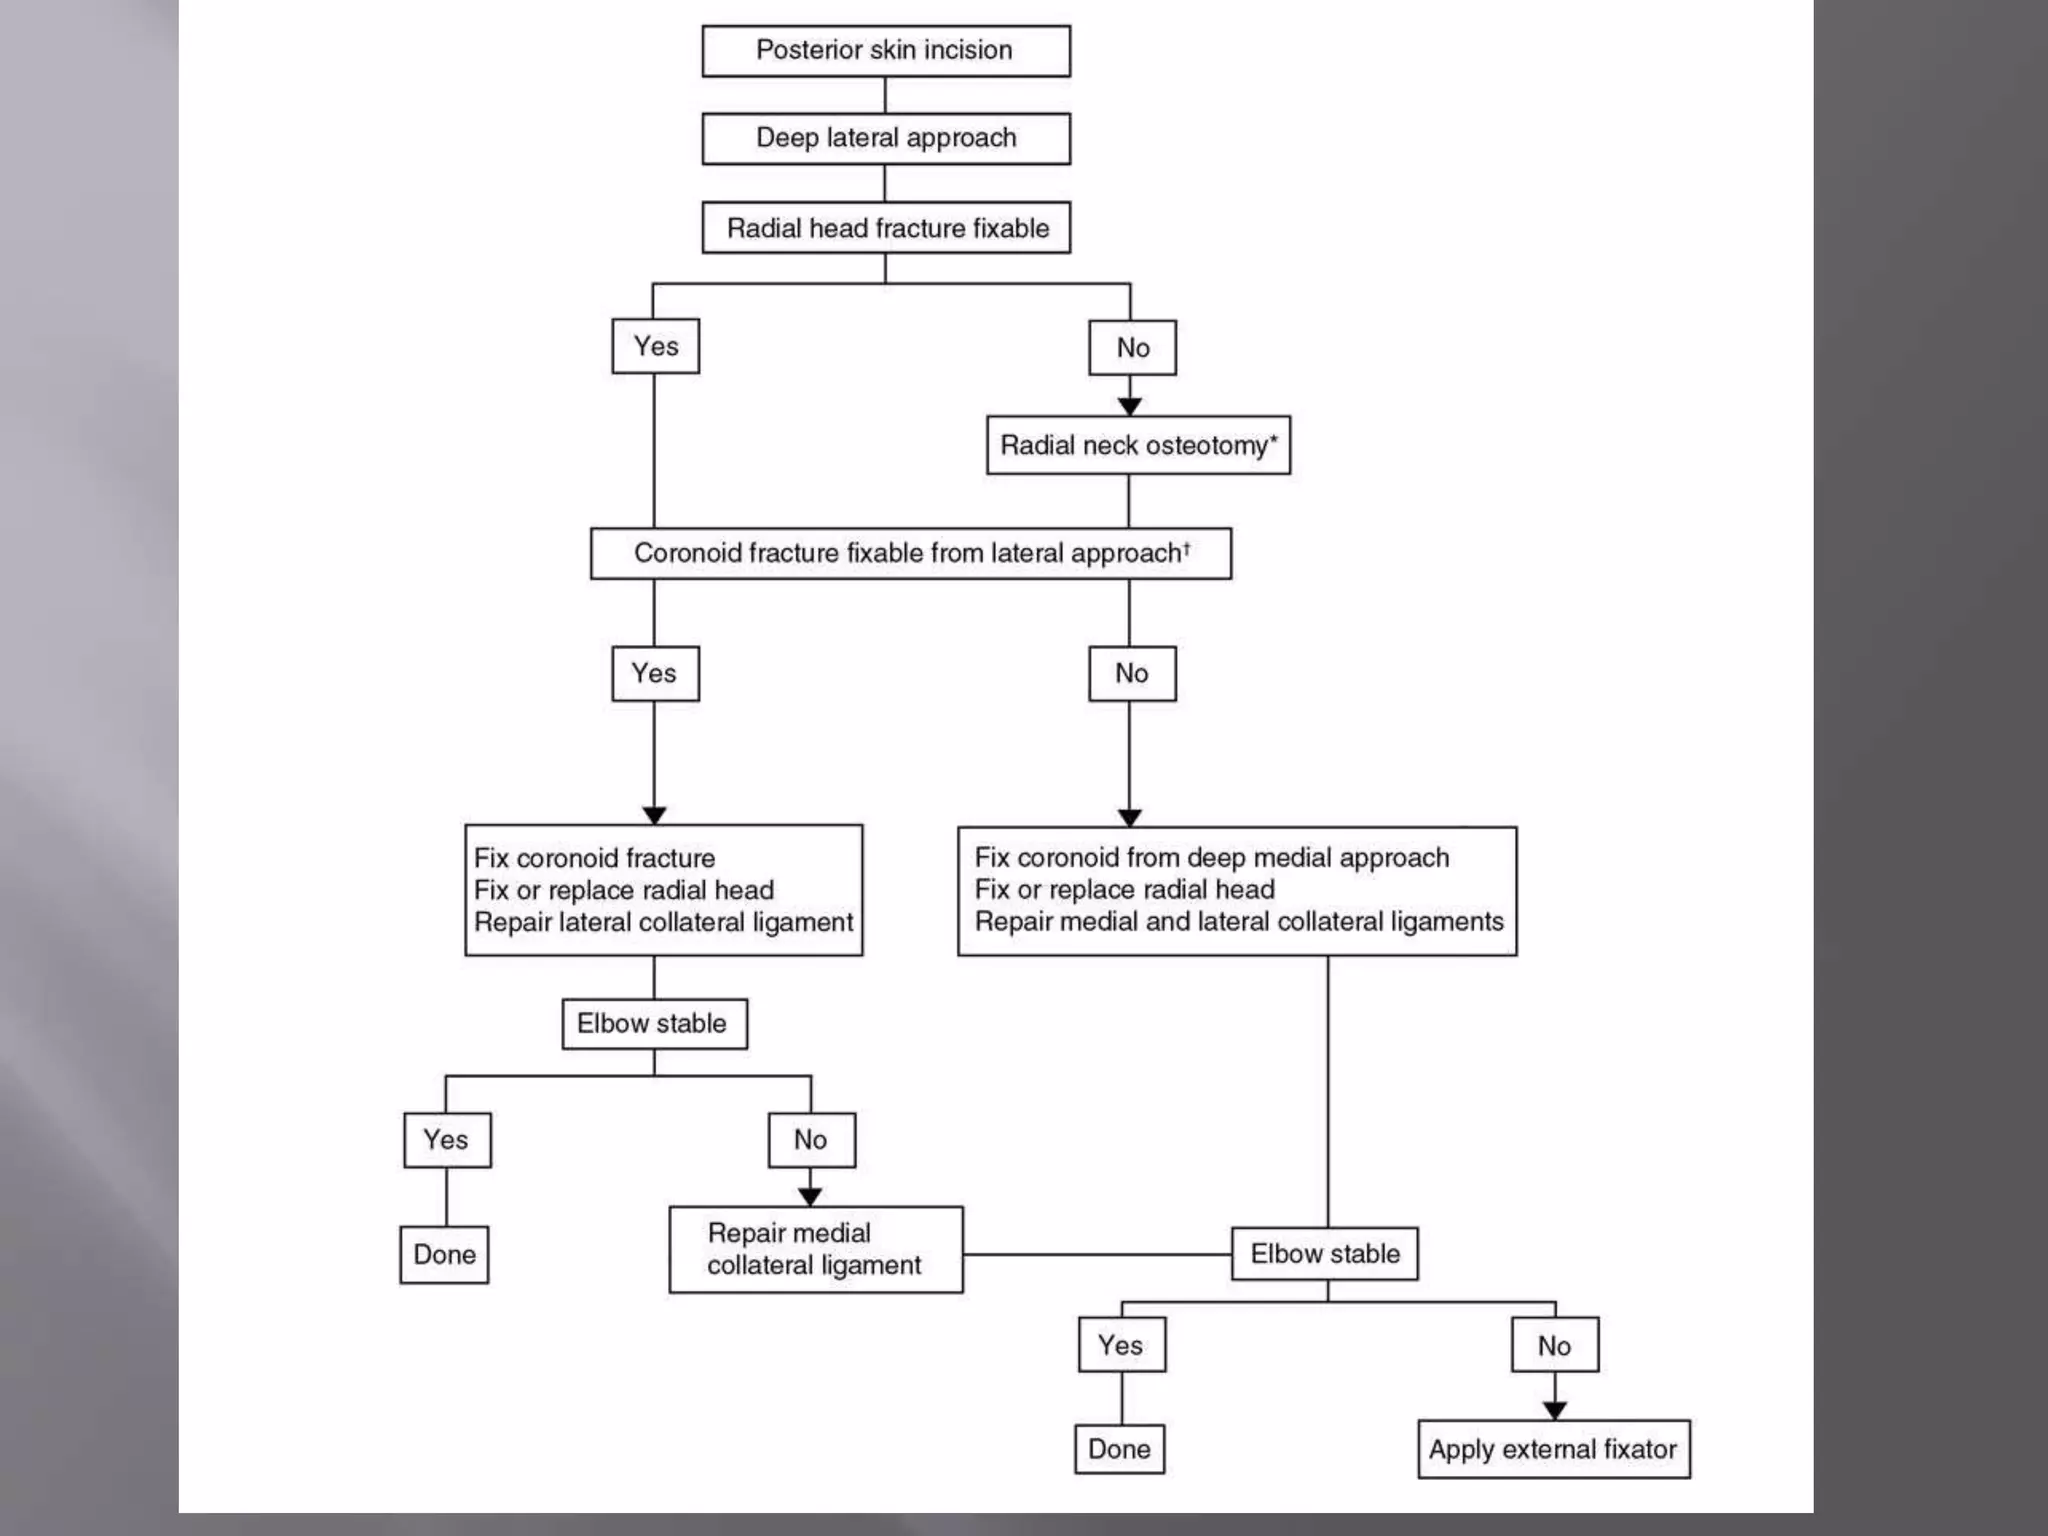

This document discusses the terrible triad injury of the elbow, which involves fractures of the radial head, coronoid process, and posterolateral dislocation. It notes the poor outcomes associated with this injury like stiffness, instability, and hardware failure. The document outlines the relevant anatomy of the medial collateral ligament and lateral uncular collateral ligament. It describes the mechanism of injury, known as the fall on an outstretched hand, and how the ligaments and capsule fail in this injury. Diagnostic imaging and classification of radial head and coronoid fractures are covered. Treatment options including observation, resection, open reduction internal fixation, and replacement are presented. Surgical approaches and techniques are also outlined.